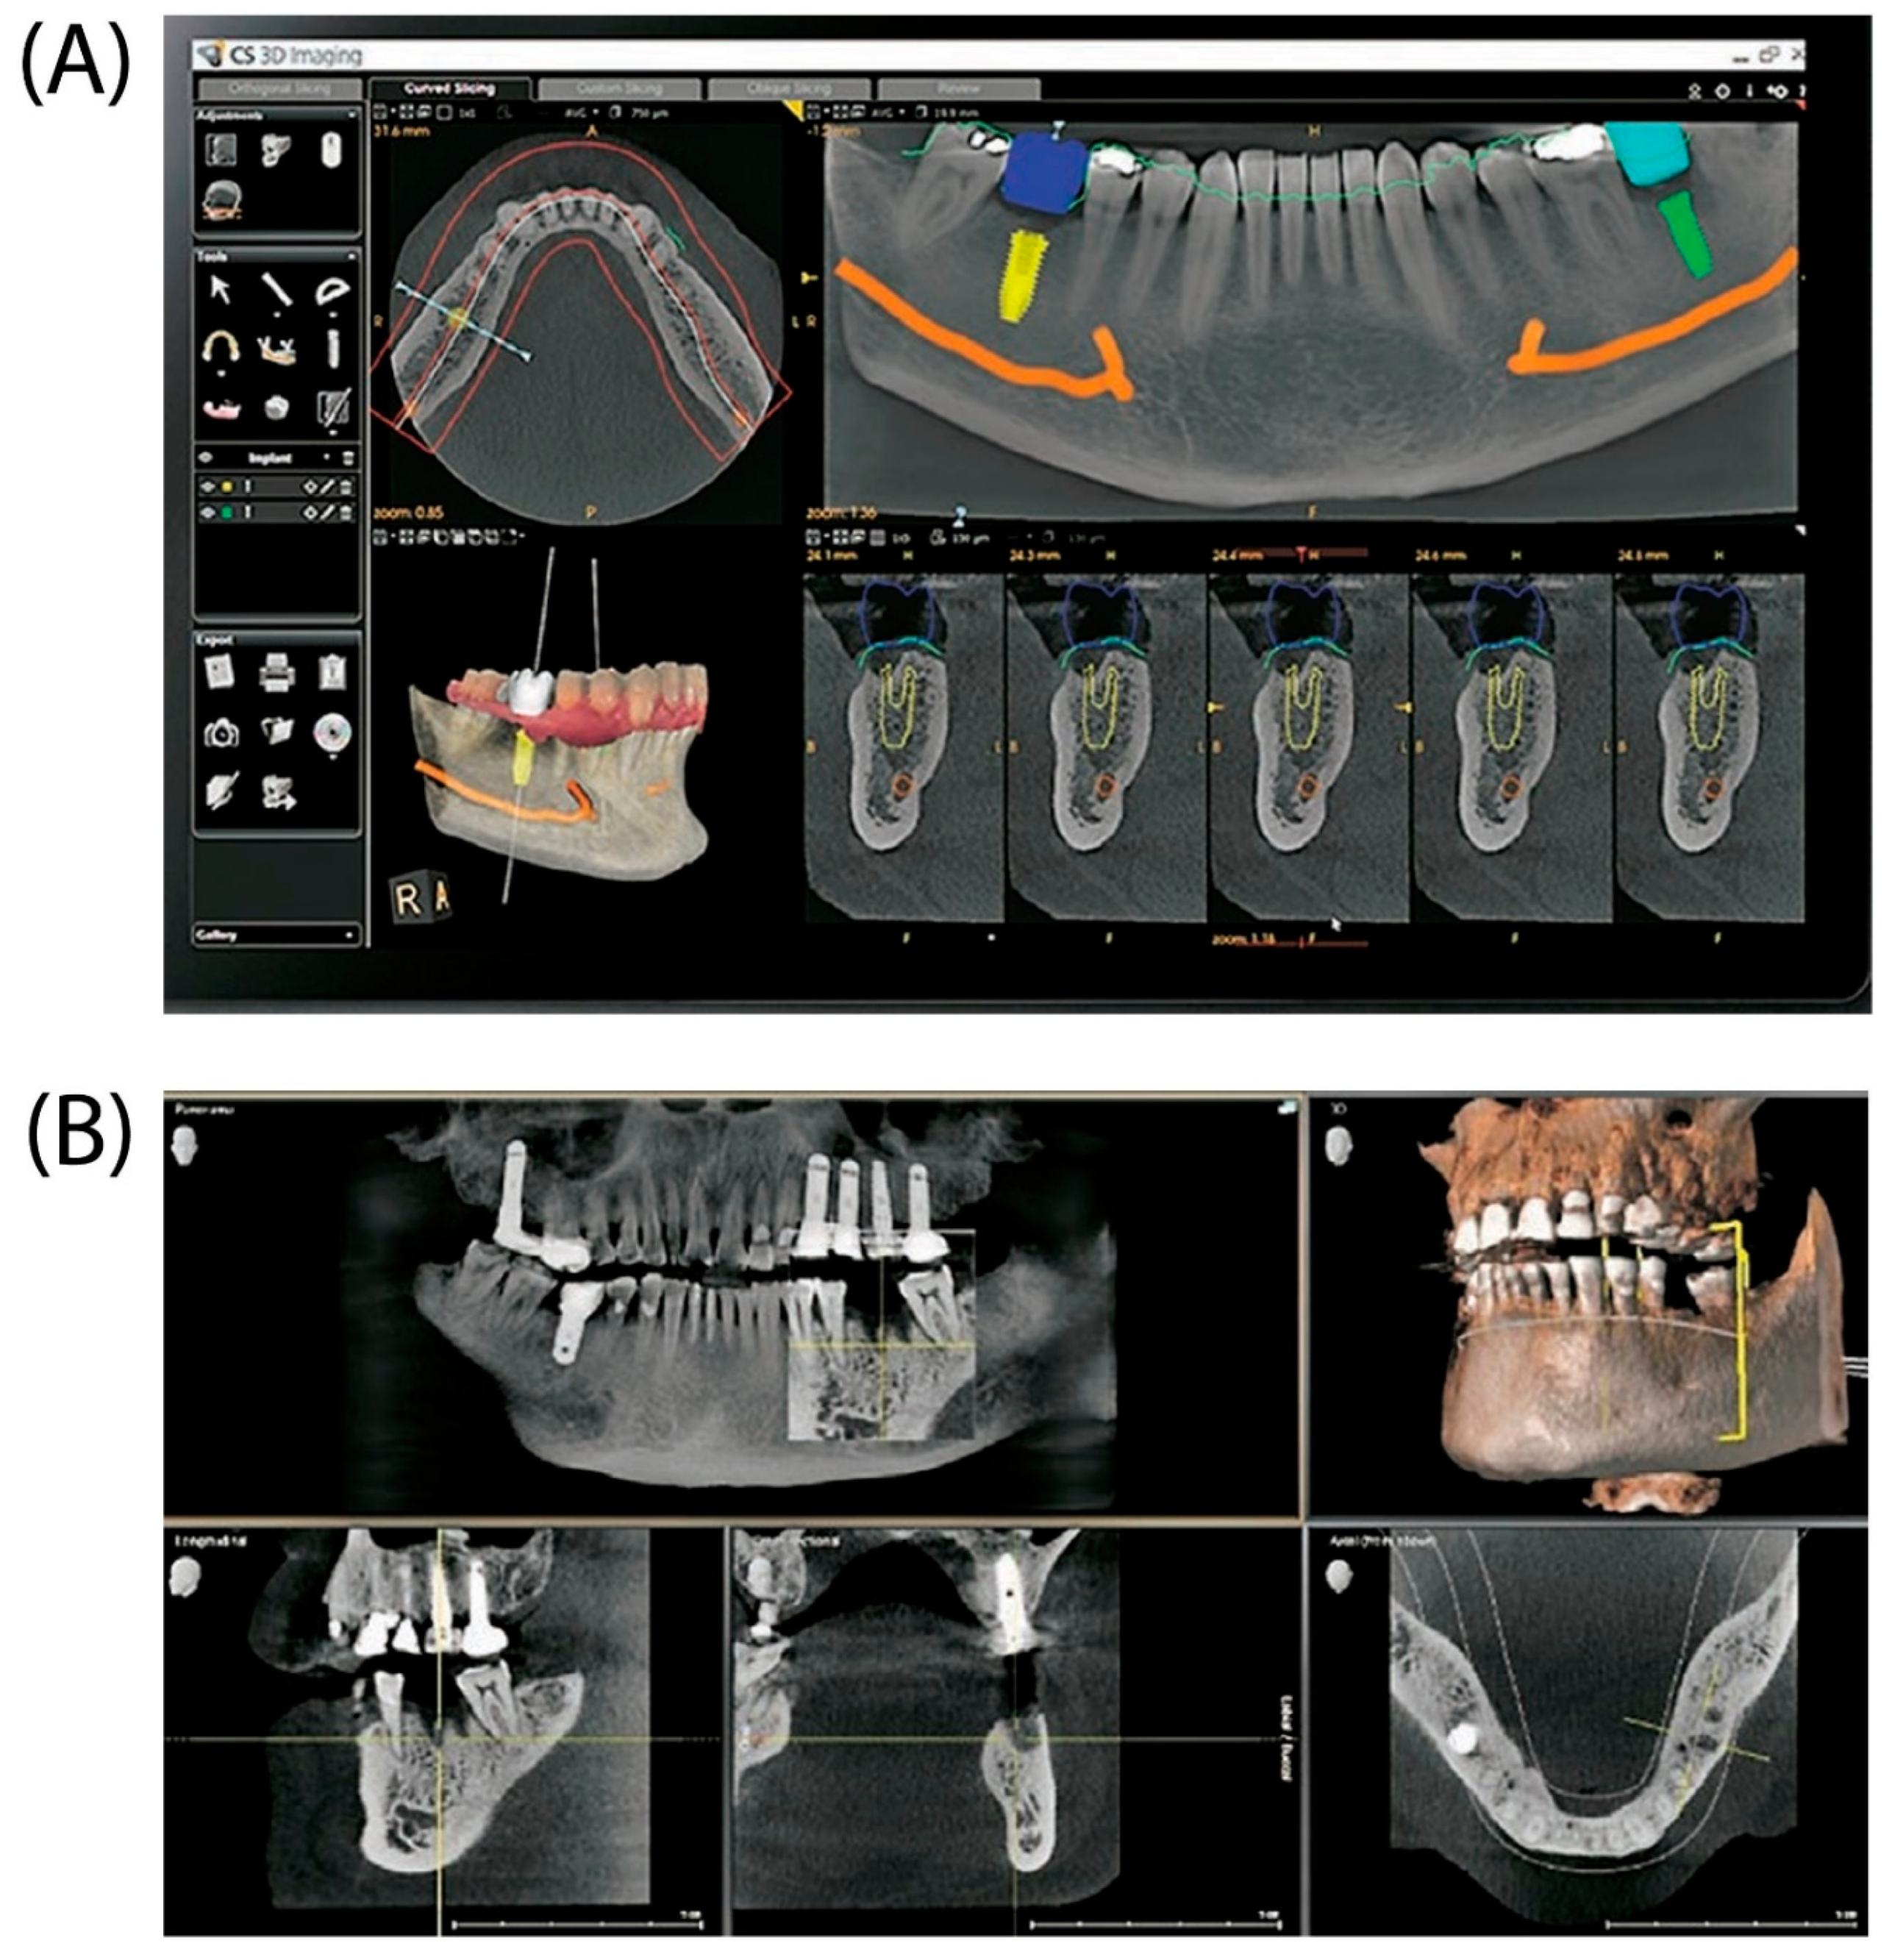

Dental implants are the major approach for replacing lost teeth because of their longevity, aesthetics, and functioning. Effective dental implant insertion requires detailed treatment planning and precision surgical execution. Three-dimensional (3D) imaging and virtual patient simulations have become effective tools for improving dental implant planning and placement accuracy (Figure 2). For excellent results and long-term patient stability, dental implant planning and surgical implantation must be performed precisely. Clinicians may evaluate a patient's oral and maxillofacial anatomy in detail and identify any possible difficulties or issues throughout the treatment with precise planning. Clinicians can create an appropriate treatment plan that reduces the risk of complications by examining the amount and quality of accessible bone, the location of neighboring teeth, and proximity to important structures such as the sinuses and nerves. Considering the patient's functional needs and aesthetic preferences, precise planning also makes it easier to choose the ideal implant size, shape, and angulation.

CBCT is frequently employed because of its advantages over traditional 2D radiology procedures. CBCT has several benefits, including the ability to generate 2D structures, 3D presentations of head and neck structures, reduced magnification error, lower radiation exposure, simpler access to scans via the DICOM standard, and fewer artifacts. The advantages listed above make implant planning and placement easier and more precise. CBCT scans the teeth and creates a computerized representation of the bone, teeth, and soft tissue. The main benefit of this approach is that it prevents nerve damage by aligning the nerve's course and selecting an appropriate implant length. Nerve damage can cause permanent or partial paralysis of the lips and chin. Choosing the appropriate implant size improves treatment success and implant longevity. CBCT allows accurate measurements for selecting the appropriate implant width and height [11].

Figure 2. (A) Illustration of a dental implant planning module featuring various visualization tools and implant placement options. (B) Images showing sagittal, coronal, and axial cross-sections with a comprehensive 3D reconstruction of the dental jaw structure [11].